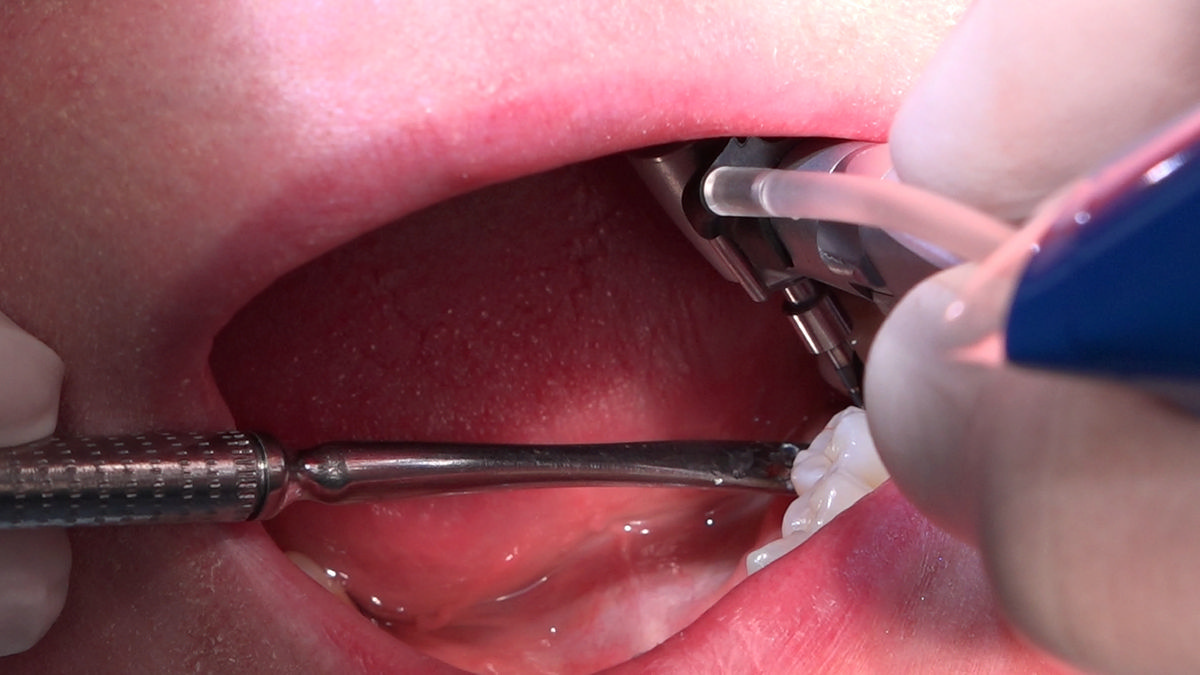

PRACTICULUM IMPLANTOLOGII - SEZON X - SESJA 4 - GRUPA B